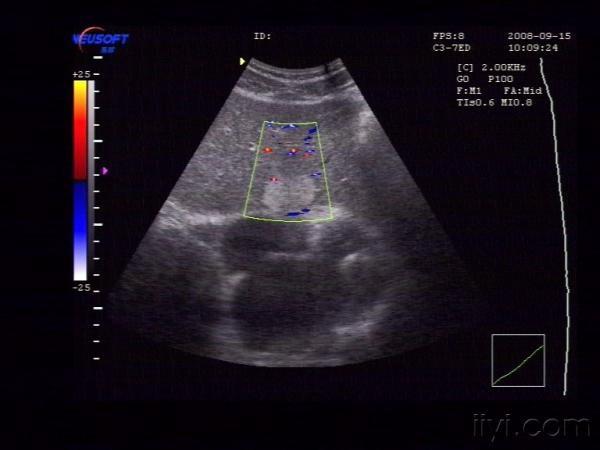

【贴图】肝脏血管瘤

体检发现左肝内一较强回声团,大小约为29X22X15mm,边界清,中央回声稍低。CDFI:未见异常血流信号

肝左叶血管瘤